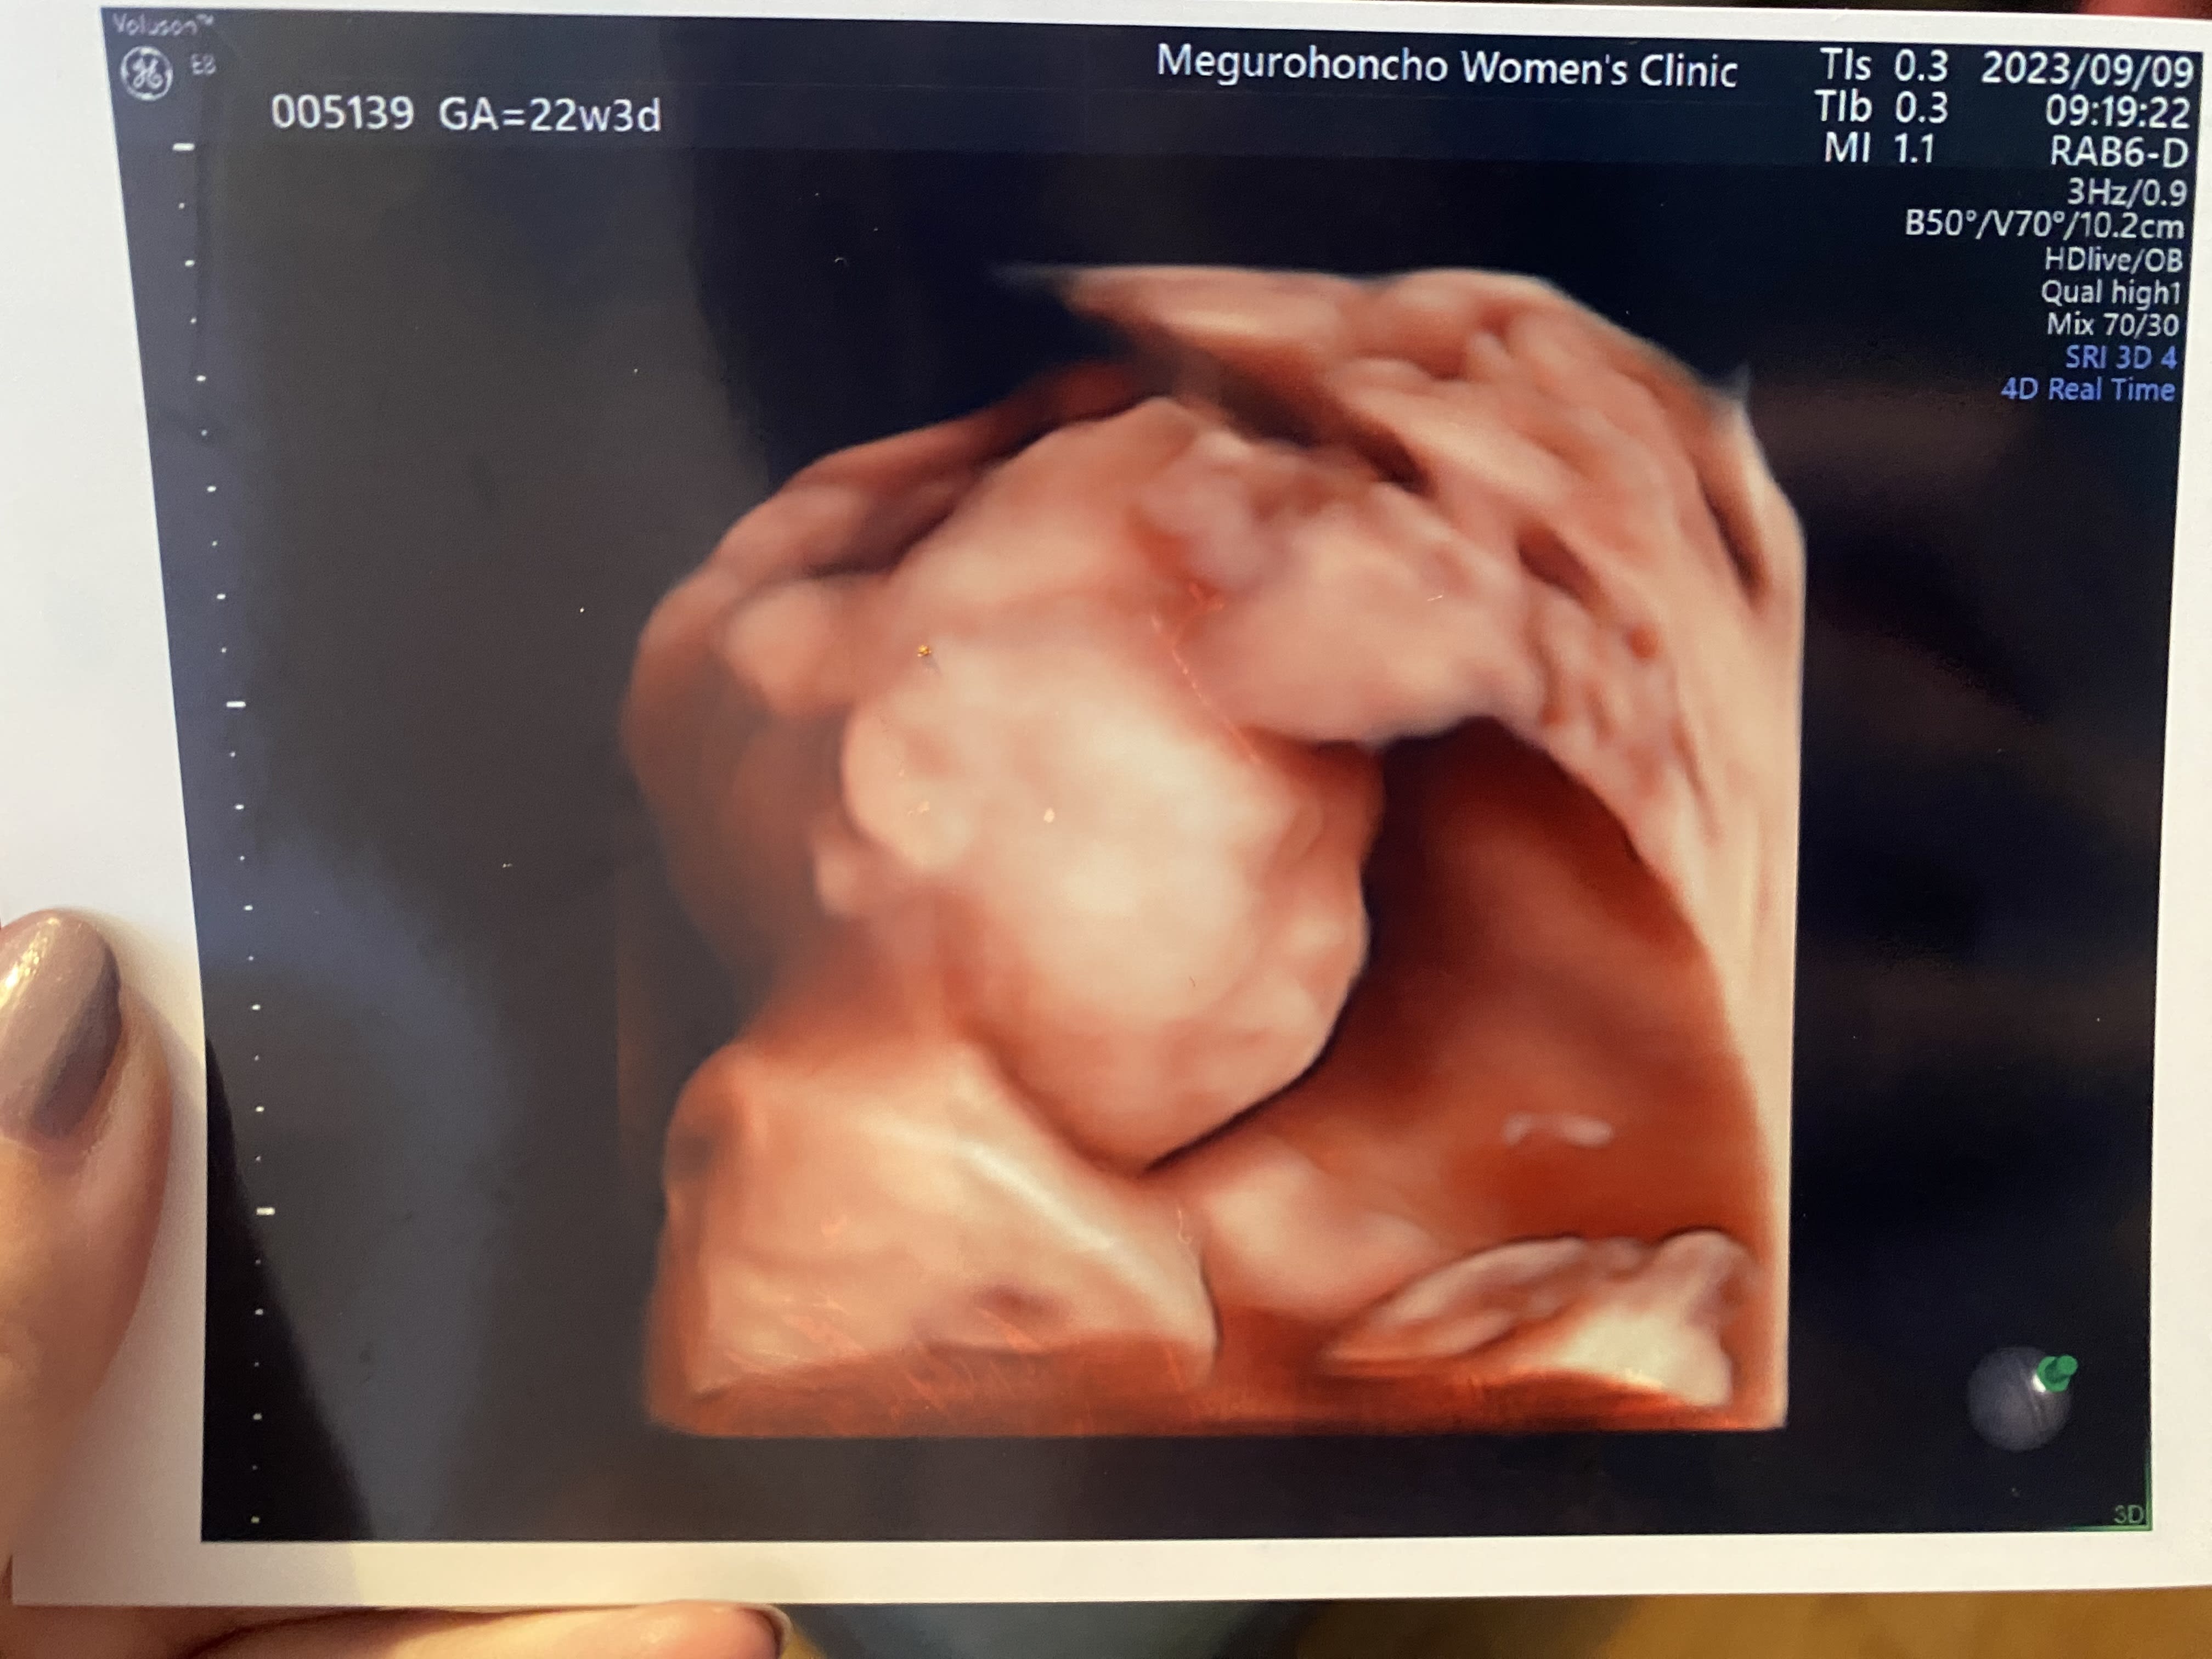

22週目のエコー写真。 鼻から顎にかけての骨格がパパに似てきたかな?

09 Sep 2023